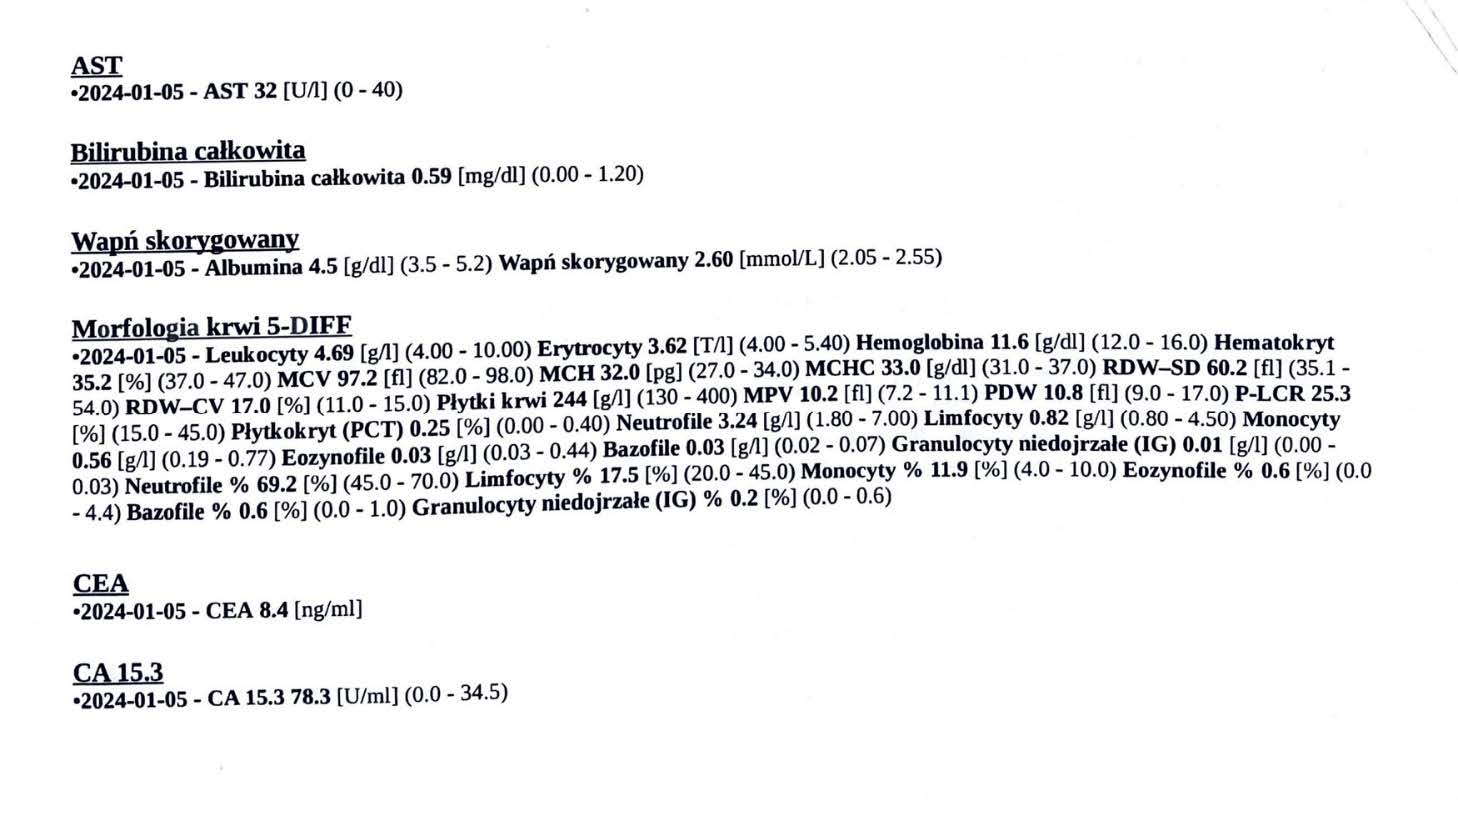

EFEKT PREPARATU NA RAKA PIERSI

Kobieta lat 71, rak piersi w IV stadium, zaawansowane stadium metastazy. W trakcie stosowania preparatu odnotowano spadek markerów Ca 15-3 z wartości 140,0 U/ml do 78,3 U/ml oraz spadek markeru CEA z 11,8 ng/ml do 8,4 ng/ml w zaledwie 3 miesiące, odnotowano stabilność szpiku. Wyniki wykazują zahamowanie progresji, dodatkowo odnotowano cechy uzupełniające terapię farmakologiczną, więc jest to jeden z przykładów wspomagania leczenia systemowego.